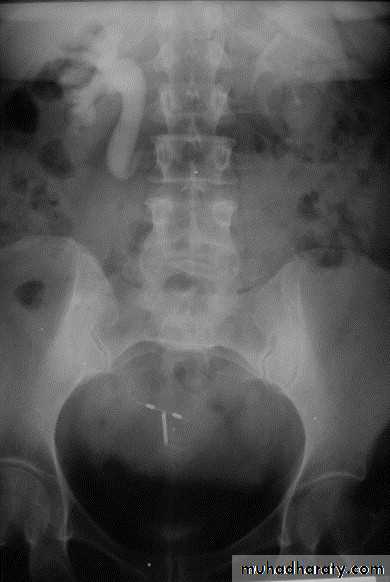

Horse shoe kidney -Kidneys may fail to separate.

-Almost invariably the lower poles remain fused.

-The kidneys axes are more parallel to the spine and malrotated.

IVU shows

1. The kidneys at low position .

2.Close to the spine with long axis parallel to the spine .

3. Malrotation manifested by medially directed calyces.

4- The renal pelvis and ureters are anterior and lateral in position .